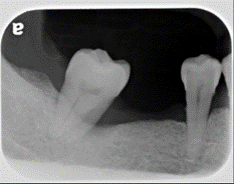

治療前X光

牙齒往缺牙處移動,開始出現縫隙。